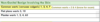

What is this infectious diseease?

What is its pathogensis ?

HSV‐1: Primary

Infection

pathogensis

❏ Usually young age

❏ Often asymptomatic

❏ Symptomatic = Primary herpetic gingivostomatitis

❏ In adults is usually pharyngotonsillitis (back of throat)

❏ Spread through infected saliva or active lesions

❏ Incubation period = 3‐9 days

These photos represent

gingivostomatitis

multiple irregularly shaped

ulcers present on the fixed and movable mucosa, bilaterally